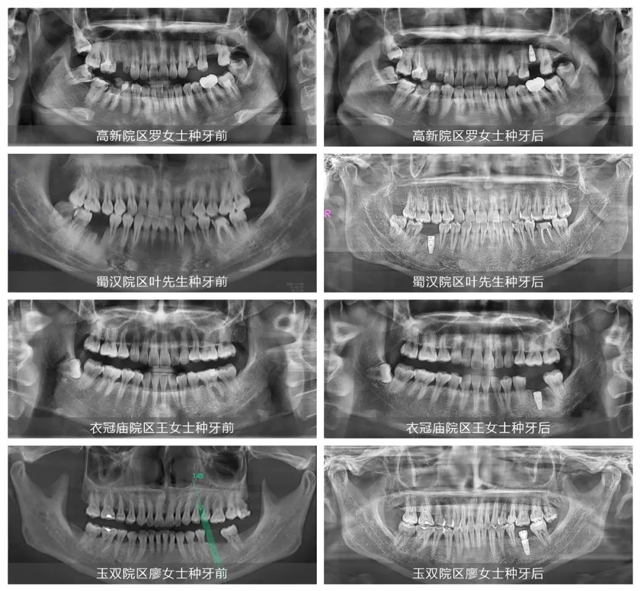

11月19日~27日,新桥口腔“种牙真功夫”数字化种植牙手术直播连续在成都高新院区、蜀汉院区、衣冠庙院区和玉双院区圆满举行,每场活动都吸引了百余缺牙市民亲临见证并通过直播平台向公众呈现!通过实时观看种牙手术、大咖医生当面答疑、种牙亲历者体验分享等环节设置,全面化解了来宾们对种牙手术的疑虑与担忧,也不断彰显了新桥口腔“种牙真功夫”。

新桥口腔种植专科以国内种植权威、华西种植专家刘果生教授和主诊专家李华领衔专家团队,医生资源规模、技术水平在整个西部口腔专科领域名列前茅。在近期的四场手术直播中——拥有20多年临床经验的高新院区种植专科主任吴建方、武大口腔种植修复硕士/蜀汉院区种植专业组副主任黄清川、新桥口腔半全口种植骨干医生孙涛及毕业于武大口腔的玉双院区种植专科主任余国庆依次担纲主刀,实力“亮剑”。

定量麻醉、逐级备洞、精准植入、严密缝合......一系列游刃有余的操作步骤,配合专业解说的精彩讲解,让现场顾客对种植牙手术有了更为全面的理解与认知。四场手术时间快则4分钟,最长也不过10分钟就圆满完成。